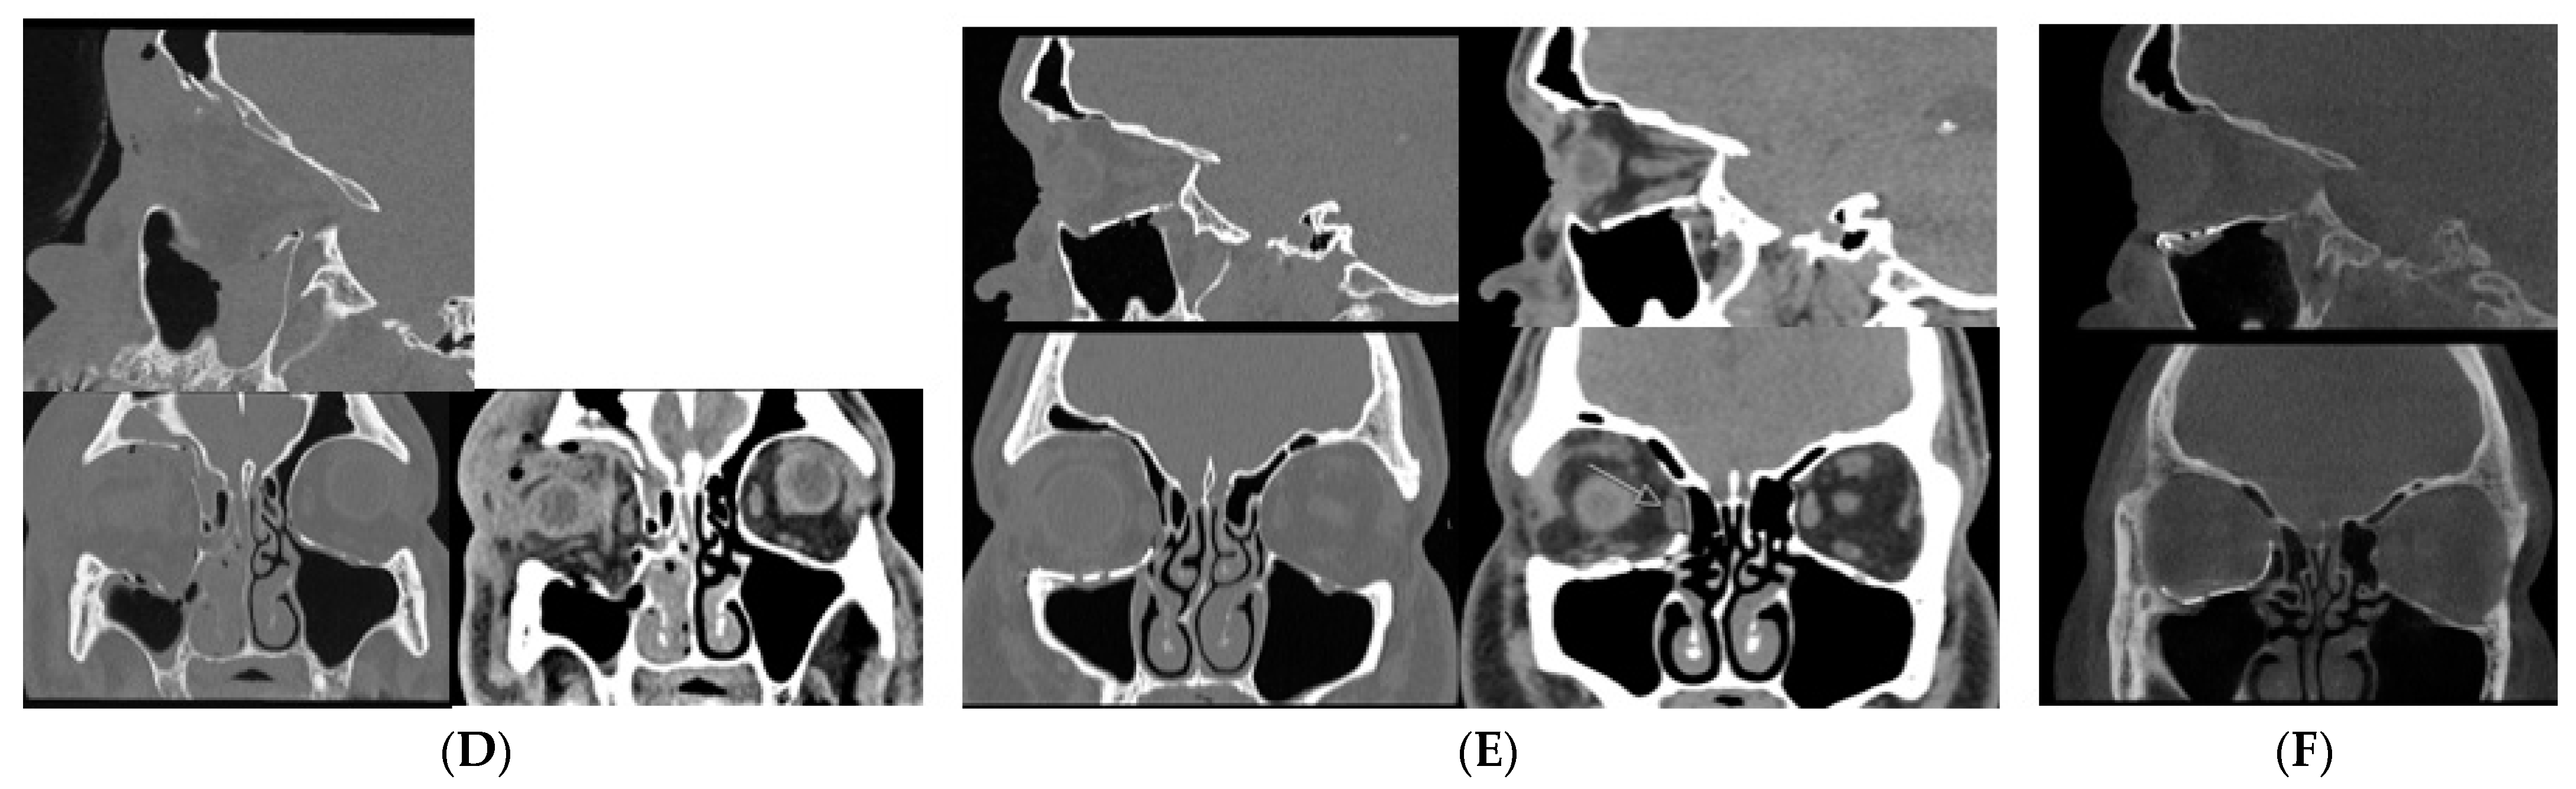

3.4. Cone Beam CT for Assessment of Orbital Fractures

3.6. Cone Beam CT for Assessment Fractures of the Zygomatic Maxillary Complex and Midface

- Roman, R.; Hedeșiu, M.; Fildan, F.; Ileșan, R.; Mitea, D.; Dinu, C.; Băciuț, M. The use of reformatted Cone Beam CT images in assessing mid-face trauma, with a focus on the orbital floor fractures. Clujul Med. 2016, 89, 519–524. [Google Scholar] [CrossRef]